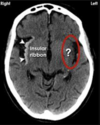

most common type of **lacunar** stroke: * often caused by occlusion of (...) artery * results in interruption of blood flow to **posterior** limb of (...) * presents with (...)

* often caused by occlusion of **lenticulostriate** artery * results in interruption of blood flow to **posterior** limb of **internal capsule** (which is where corticobulbar and corticospinal fibres pass through) * presents with **CONTRALATERAL hemiparesis** of **(lower) face, arm and leg**